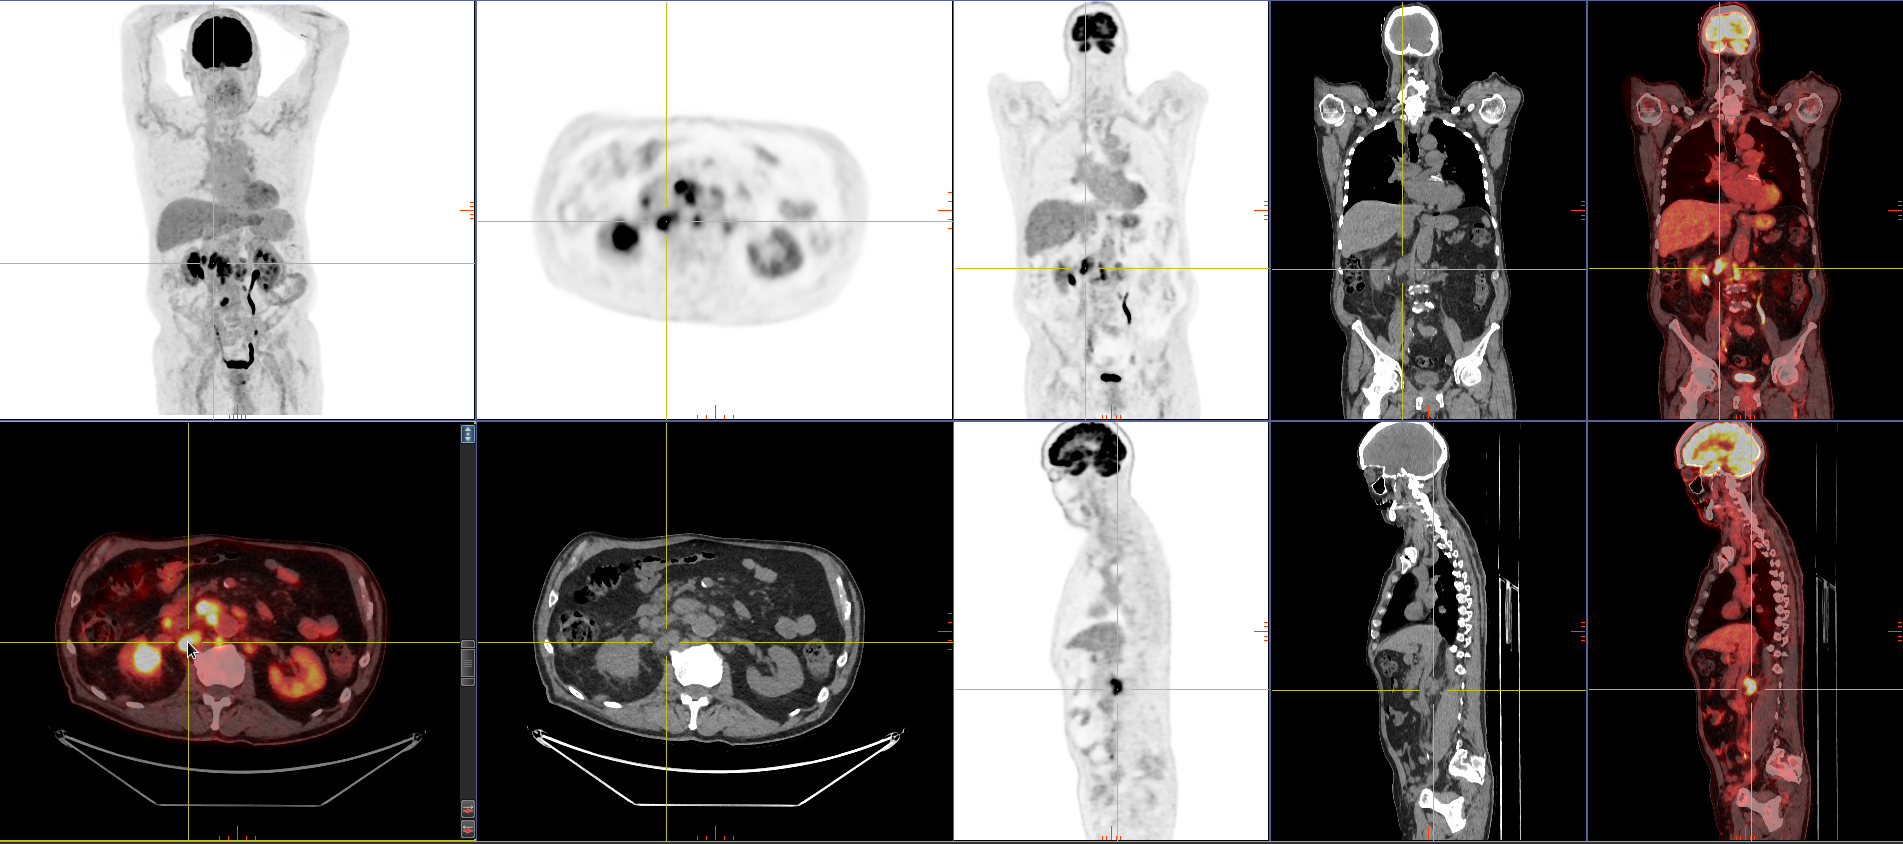

PET Scans for Rare & Uncommon Cancers – Are You Referring Eligible Patients?

At SRNM, we offer Medicare-funded FDG PET scans (Items 61612 & 61614) for the staging, treatment response, and recurrence of rare and uncommon cancers.